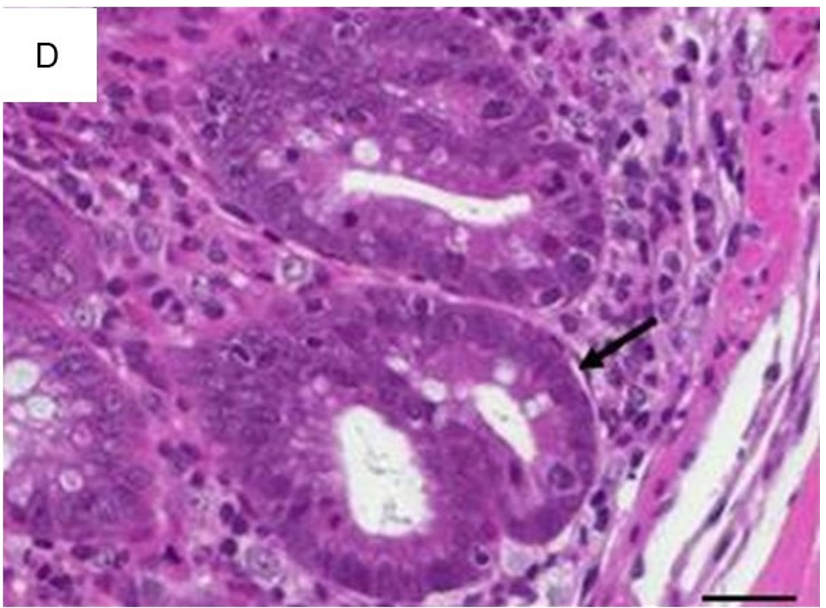

白细胞浸润固有层,这是所有肠炎模型的共有特征。尽管浸润了不同比例的嗜中性粒细胞、嗜酸性粒细胞、单核细胞、浆细胞和淋巴细胞,评估每高倍视野(HPF)组织内混合的炎症细胞,可充分反映了炎症相关的变化(图1A)。散在中性粒细胞是轻度浸润的典型特征(图1B)。从炎症细胞的主要局部粘膜定位开始(图1C),严重程度增加首先包括粘膜下层(图1D),随后延伸至固有肌层并最终导致透壁浸润(图1E)。最初见于上皮细胞层的主要变化包括隐窝上皮细胞增生,杯状细胞的损失,隐窝炎、隐窝脓肿和糜烂。

1(D)炎症细胞的粘膜和粘膜下层(箭头)浸润(×100,比例尺100µm)